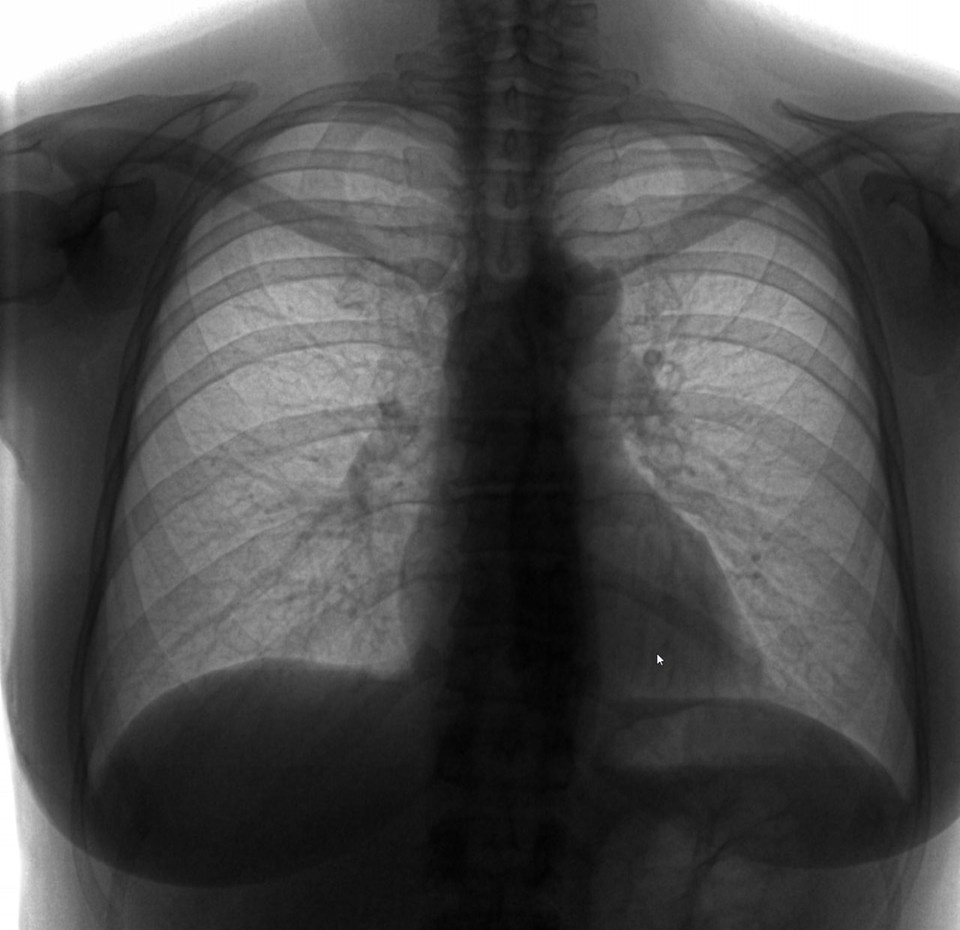

Так выглядят легкие здорового человека. Фото из личного архива.

Флюорографию чаще всего применяют для обследования легких. Она помогает выявить воспалительные и инфекционные заболевания легких, в том числе туберкулез.

Рентгенографию легких назначают при подозрении на пневмонию различного генеза, наличие жидкости или воздуха в плевральной полости, острые тромбозы (ТЭЛА). С помощью рентгенографии брюшной полости определяют кишечную непроходимость и наличие свободного газа в желудочно-кишечном тракте. Рентгенография костно-суставной системы помогает обнаружить изменения, переломы, вывихи, новообразования.